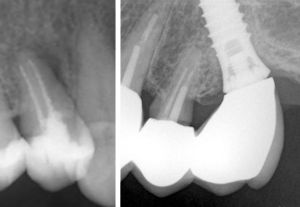

19.1.26: Der -7 wurde beim Pressen stark belastet und hat stark geschmerzt.

Beide apikalen Aufhellungen sind sehr klein.

Ist die Ursache bakteriell oder nur mechanisch?

Die Patientin spürt, dass sie häufig ihre Zähne zusammenpresst. Deswegen hatte sie am 19.1.26

starke Schmerzen links unten.

Am 22.1.26 waren diese verschwunden, dafür schmerzte nachher die Wange links oben.

Bei den oberen Molaren zeigt das Röntgenbild keine Aufhellung.

Ist der -7 entzündet und braucht er eine Wurzelbehandlung?

Stattdessen hab ich ihr eine FOS-Knirscherschiene gemacht. Diese wird zeigen, ob die Beschwerden wieder aufhören.

Die Patientin hat einen Nachtbruxismus und spürt morgens verspannte Wangen. Sie hat nur Kontakt auf den hintersten Molaren und keine Schmerzen. Das reibende Geräusch ist wahrscheinlich eine stabile Diskus-Degeneration und braucht keine Behandlung.